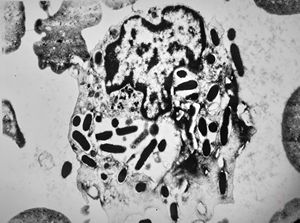

M,43y. | blood - degraded Candida (bone marrow suppression)

M,18y. | blood - clin. susp. leukemia - degraded Candida